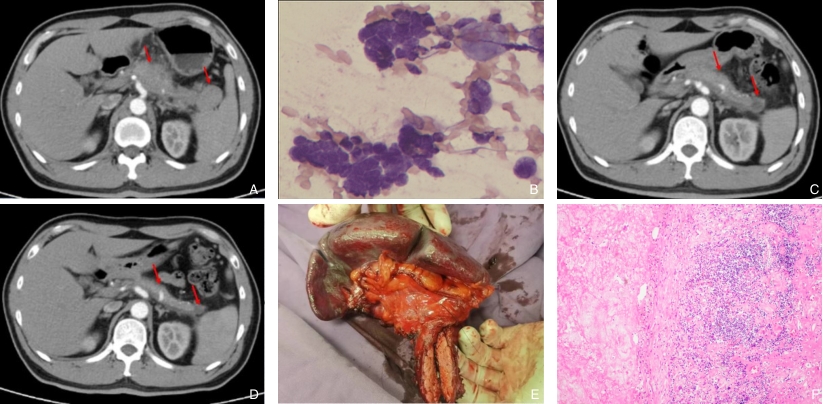

图2 病例2资料 A:初次就诊CT示胰腺体部体积增大,轮廓不规则且局部膨隆,腹腔干及脾动静脉受累,另胰尾部及脾脏周围间隙见多发结节及肿块影;B:EUS-FNA病理结果;C:HIFU+新辅助化疗2个月后复查,胰腺占位较前缩小,血管受累较前改善;D:HIFU+新辅助化疗4个月后复查,胰腺占位较前明显缩小,病灶内以坏死为主,血管受累进一步改善;E:手术大体标本(胰体尾+脾脏切除),肿块中间见大量坏死组织;F:手术标本病理结果(HE×200)Fig.2 Clinical data of case 2 A: Initial contrast-enhanced CT showing enlargement and focal bulging of the pancreatic body with encasement of the celiac axis and splenic vessels, and multiple nodular or mass-like lesions around the pancreatic tail and spleen; B: Pathological findings from EUS-FNA; C: Follow-up imaging 2 months after HIFU combined with neoadjuvant chemotherapy showing tumor shrinkage and improved vascular involvement; D: Follow-up imaging 4 months after combined therapy showing further tumor reduction and predominant intratumoral necrosis with continued improvement in vascular encasement; E: Gross specimen of distal pancreatectomy with splenectomy showing extensive central necrosis; F: Histopathological findings of the surgical specimen (HE×200)